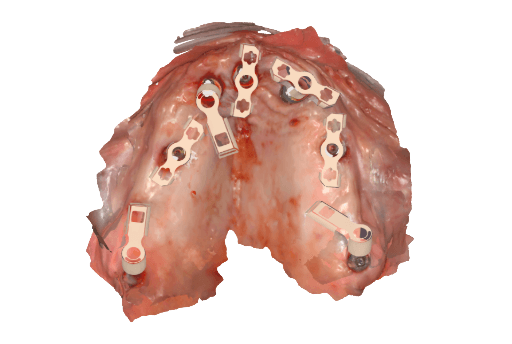

During the second appointment, the surgical implant placement was performed. Using the 3D printed surgical guides, seven implants were placed in the upper arch and six implants in the lower arch. The surgery was performed under local anesthesia using a flapless approach in both arches. Total surgical time was approximately 45 minutes. No intraoperative complications were observed.

3D printed surgical guide with fixation pins

Seven implants placed

Upper arch surgical procedure. From left to right: Pre-surgical intraoral situation, 3D printed surgical guide with fixation pins, and seven implants placed.